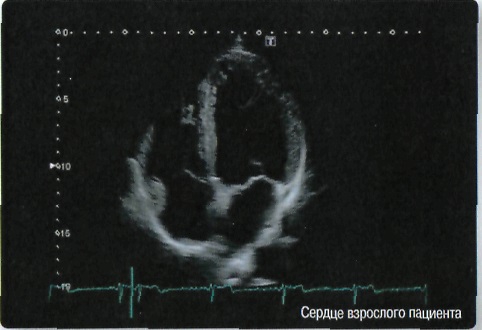

• STIC - исследование сердца плода в режиме объёмной визуализации

• STIC Color - цветная объёмная визуализация сердца плода

Кардиология:

Да

• Стресс-эхо исследования с фармакологической и физической нагрузкой;

• Отображение физиологической информации ЭКГ/ФКГ (фонокардиографии - графической регистрации сердечных тонов и шумов);

• Программа анализа сердца плода в трех проекциях в реальном времени 4D Stick;